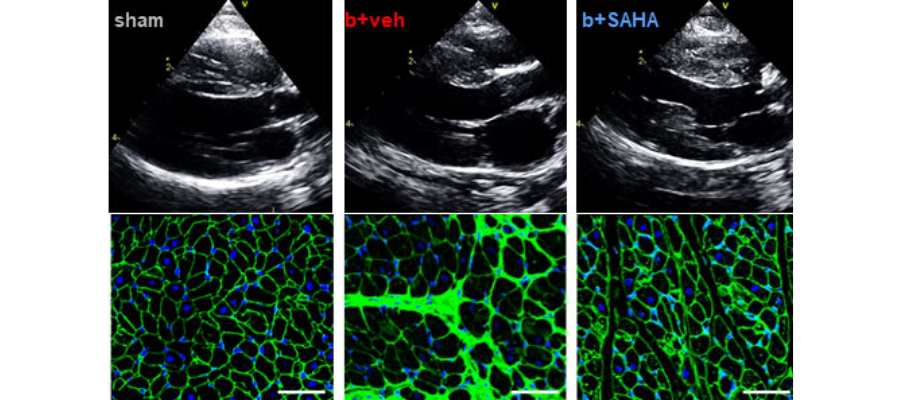

First row: Representative echocardiography images showing left ventricle wall thickness and left atrium size.

Second row: Cross-sectional tissue sections stained with wheat-germ agglutiin (WGA) and DAPI. WGA stains the border of the cardiomyocytes green and DAPI stains the nucleus blue.

Following treatment with SAHA, HFpEF animals showed amazing improvements. In particular, hypertrophy of the left ventricle was significantly reduced in treated compared to untreated animals. The left ventricle was also much more relaxed in treated animals, enabling the heart to fill and pump more effectively and leading to overall improvements in heart structure and function.